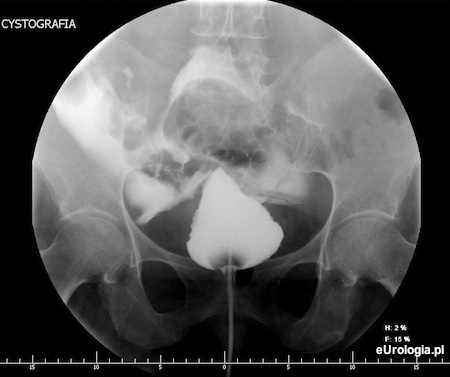

Perforację pęcherza moczowego rozpoznaje się na podstawie badania klinicznego, które uzupełnia się badaniami obrazowymi takimi jak USG jamy brzusznej lub cystografia. Cystografia jest najczęściej wykonywanym badaniem w diagnostyce urazów pęcherza moczowego. Cystografia jest badaniem obrazowym polegającym na podaniu środka kontrastowego przez cewnik do pęcherza moczowego i wykonaniu zdjęć rentgenowskich lub skanów tomografii komputerowej. W przypadku przebicia ściany pęcherza moczowego w cystografii widoczny jest wyciek kontrastu do jamy otrzewnowej.

Fot. Cystografia wykonana u pacjentki z perforacją dootrzewnową pęcherza moczowego.